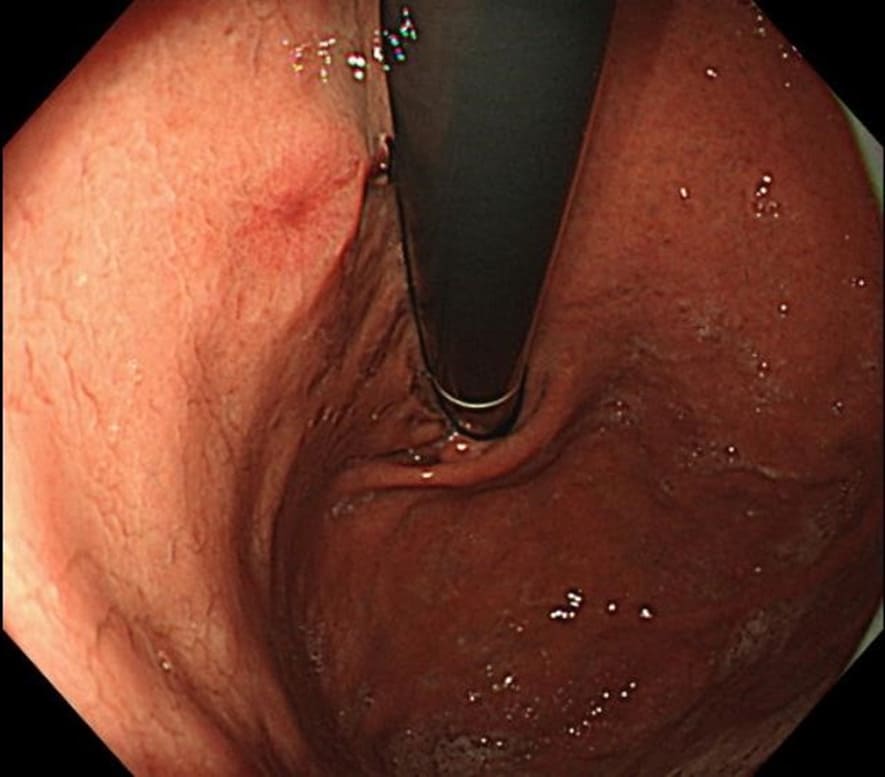

Our patient was a man in his eighties who was referred to our department after a screening endoscopy indicated some abnormalities. Upper gastrointestinal (GI) endoscopy revealed a 6-mm submucosal tumor in the posterior wall of the lesser curvature of the upper gastric body. A very slightly depressed erosion was observed at the apex see in (Figure 1).

Figure 1: Upper gastrointestinal (GI) endoscopy. A submucosal tumor-like flat protrusion with a central depression is observed on the posterior wall of the lesser curvature of the upper gastric body.